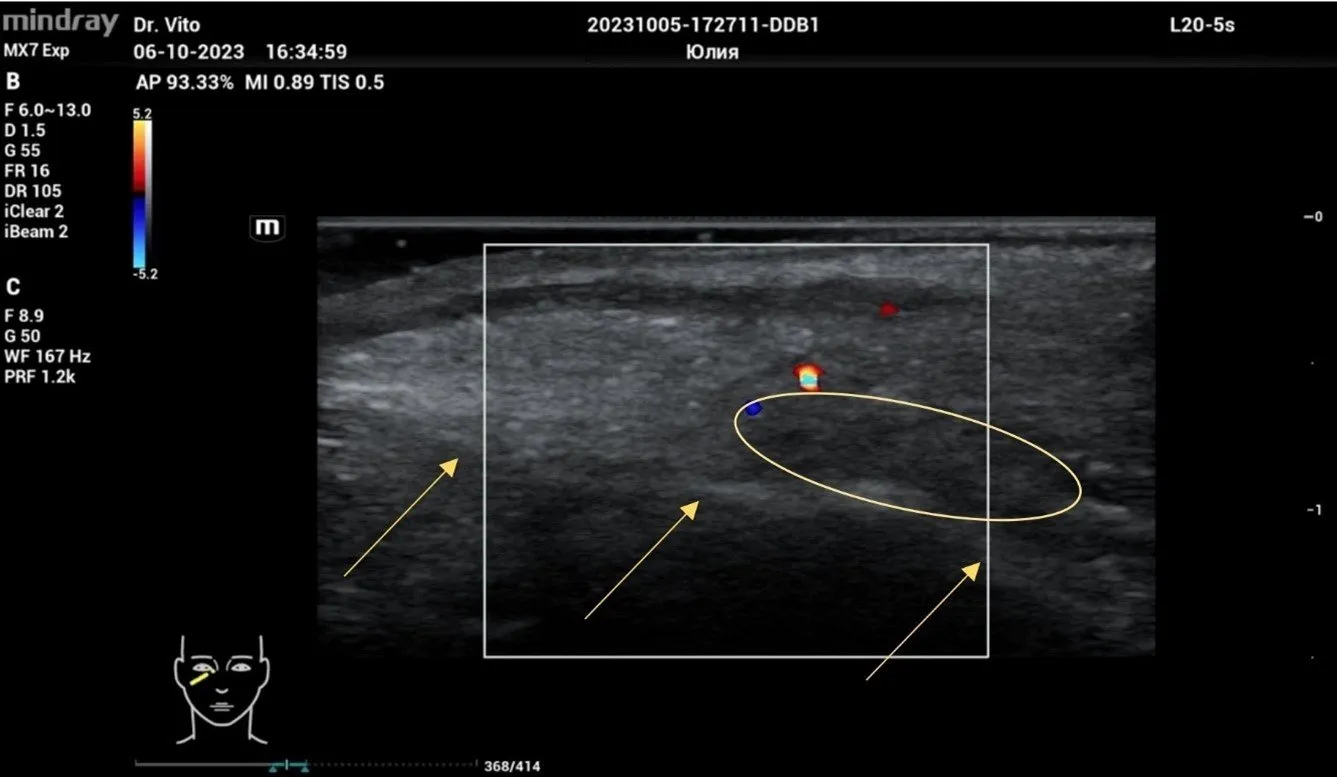

На серии УЗ-снимков хорошо визуализируется канюля 25G * 50 мм, которая находится в слое между орбитальной септой и круговой мышцей глаза над надкостницей края орбиты, что является оптимальной топографией для введения филлера и получения максимально эффективного результата. Стоит отметить абсолютную безопасность коррекции филлеров ввиду визуализации всех крупных сосудистых образований, которые легко обойти канюлей без травматизации и риска эмболии.

Рисунок 2. Филлер на основе ГК, сразу после процедуры обозначен овалом. Стрелками обозначена надкостница